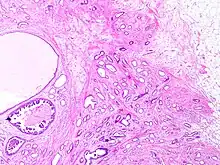

Histopathology of tubular carcinoma, high magnification, H&E stain. It shows the typical features of tubules lined by a single layer of cuboidal to columnar epithelial cells with small to intermediate sized nuclei low grade nuclei and sparse mitoses (grade 1).[1]

Tubular carcinomas are generally around 1 cm. or smaller, and are made up of tubules. They are usually low-grade.[2] Elastosis has been noted as common but is not present in all cases.[11]